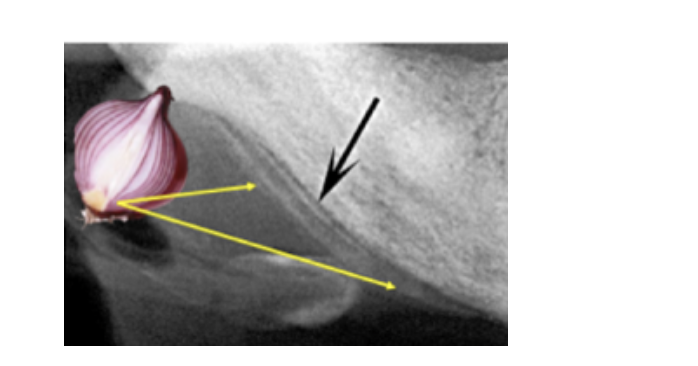

Chronic Osteomyelitis

A

Diffuse Mottled Radiolucency

Garre’s Osteomyelitis:

* Chronic Osteomyelitis w/proliferative periosteitis (onion skin)

Tx: ANtibiotics & debridement of infected area